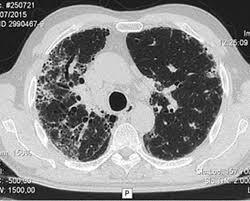

Es una opacidad lineal o en red que ocurre por ocupación de agua, colágeno o enfermedad del intersticio en la barrea alveólo-capilar:

Patrón intersticial o reticular

¿Cómo se ve el patrón intersticial o reticular en rx y TC?

Líneas finas o gruesas en los extremos del pulmón